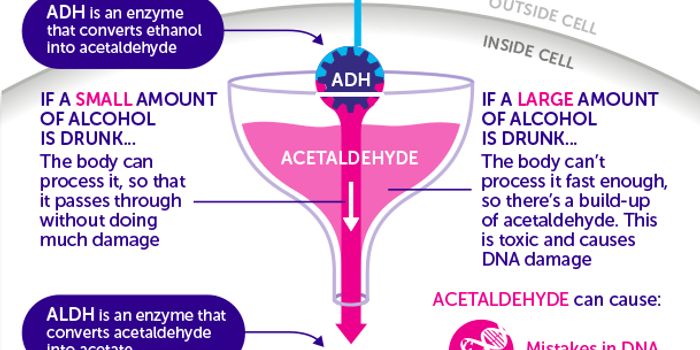

JAN 09, 2018Cancer"This paper provides very strong evidence that an alcohol metabolite causes DNA damage [including] to the all-important ...